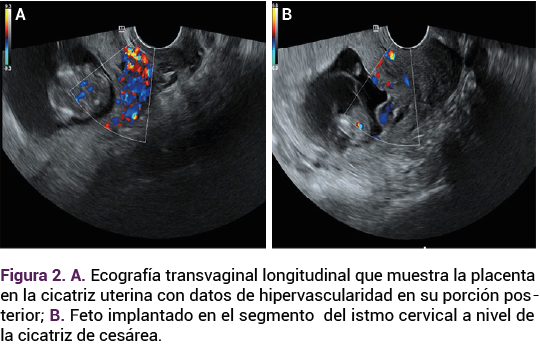

El fondo uterino se encontró vacío y al feto en el segmento inferior, la placenta cubría el orificio cervical interno, con vasculatura anormal hacia el segmento, con impresión diagnóstica de embarazo ectópico ístmico-cervical (Figuras 2A y 2B).

<strong>Figura 2</strong>A

Figura 2A. | Figura 2B.